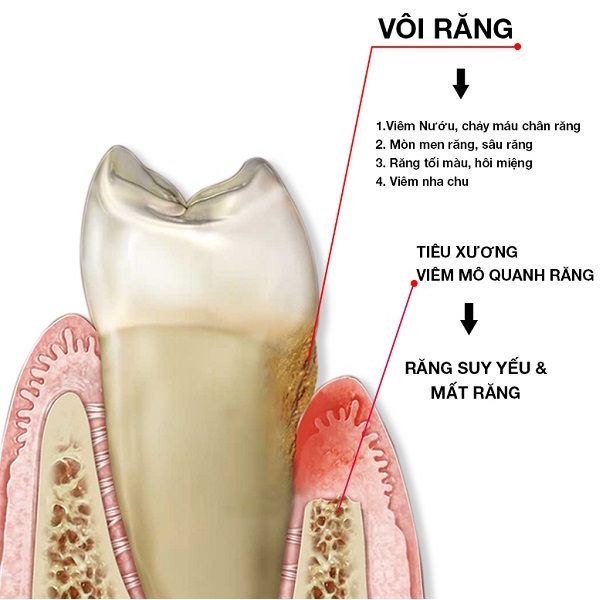

VÔI RĂNG (CAO RĂNG) NGUY HIỂM NHƯ THẾ NÀO?

Vôi răng (cao răng) thực chất là những mảng bám do thức ăn bám trên răng lâu ngày bị vôi hóa và kết hợp với canxi carbonat và phosphate có trong nước bọt. Vôi răng gồm một phần nhỏ trên thân răng (nơi chúng ta nhìn thấy) nhưng phần lớn chúng lại nằm ở chân răng và phần răng dưới nướu (chúng ta khó nhìn thấy phần vôi răng này nhưng nó là phần nguy hại nhất).

Những nguy hiểm do vôi răng gây ra mà phần lớn chúng ta không biết:

(Vôi răng gây ra nhiều bệnh răng miệng nguy hiểm hơn chúng ta tưởng)

Vôi răng là nơi lý tưởng nhất để vi khuẩn tích tụ từ đó gây ra các bệnh: viêm nướu, viêm nha chu, hôi miệng, acid phá hủy men răng, sâu răng và sâu răng có viêm tủy. Nguy hiểm bậc nhất trong các bệnh do vôi răng đó là viêm nha chu. Viêm nha chu là bệnh vô cùng phổ biến tại Việt Nam và nó gây nên hiện tượng: viêm xung huyết nướu, viêm mô quanh răng, tụt nướu, tiêu xương hàm, ... dẫn đến răng yếu, lung lay và mất răng sớm.

Viêm nha chu do vôi răng còn dẫn đến nguy cơ các bệnh: đau vùng thái dương, tim mạch, nhiễm khuẩn huyết, tiểu đường, bệnh về đường hô hấp, sinh non nhẹ cân, …